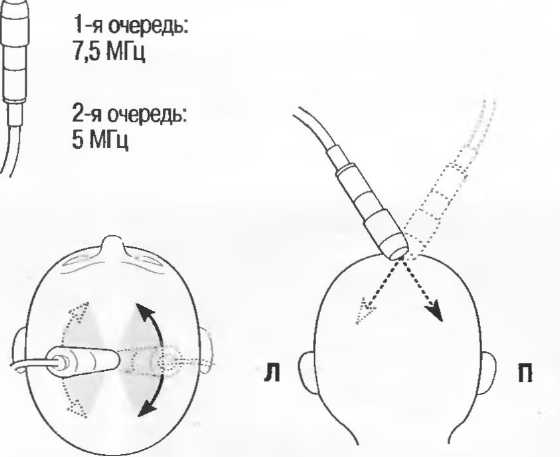

2. Ультразвуковые исследования в общей практике. Если проводятся исследования в верхней части живота и таза у взрослых, в том числе и акушерские исследования, предпочтительнее выбор секторного или конвексного датчиков с частотой 3,5 МГц с глубиной фокусировки на 7-9 см.

3. Ультразвуковые исследования в педиатрии. Для детей необходим датчик с частотой 5 МГц с глубиной фокусировки на 5-7 см. При исследовании мозга новорожденного используется секторный датчик с частотой 7,5 МГц с глубиной фокусировки на 4-5 см (этот датчик также используется для исследования яичек и структур шеи у взрослых).